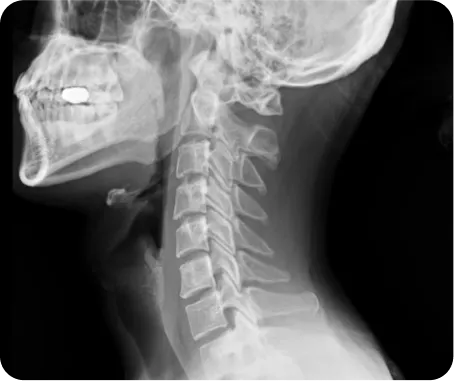

▲ 척추관협착증 환자의 CT

정상목 5kg

목뼈가 받는

하중

일자목 22.2kg

약 4.5배

일자목을 가진 사람이 받는 하중은

정상목의 약 4.5배이기 때문에

교통사고 시 발생하는 충격도

더 크게 발생하게 됩니다.

그래서 일자목인 환자의 교통사고 후유증 치료는

그 방법과 치료 기간이 다를 수밖에 없습니다.